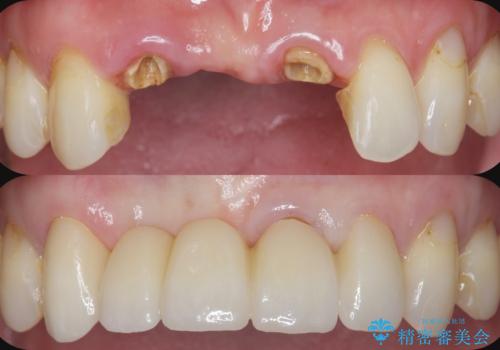

工程数が多かったため治療期間はかかりましたが、しっかりと安定した噛み合わせ、審美的な口腔内環境を達成することができ大変満足していただくことができました。

全顎的 虫歯治療 インプラント補綴

今後延々と治療を繰り返さないために、全ての銀歯を外し虫歯を丁寧に取り切り、根管治療を行い、残せない歯は抜去を行った上でインプラント治療を行っていくことで全体的な治療を計画していくこととなりました。